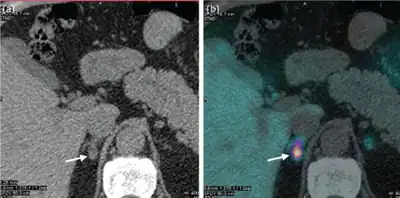

If primary hyperaldosteronism is confirmed biochemically, CT scanning or other cross-sectional imaging can confirm the presence of an adrenal abnormality, possibly an adrenal cortical adenoma (aldosteronoma), adrenal carcinoma, bilateral adrenal hyperplasia, or other less common changes. Imaging findings may ultimately lead to other necessary diagnostic studies, such as adrenal venous sampling, to clarify the cause. It is not uncommon for adults to have bilateral sources of aldosterone hypersecretion in the presence of a nonfunctioning adrenal cortical adenoma, making adrenal venous sampling mandatory in cases where surgery is being considered.[17]